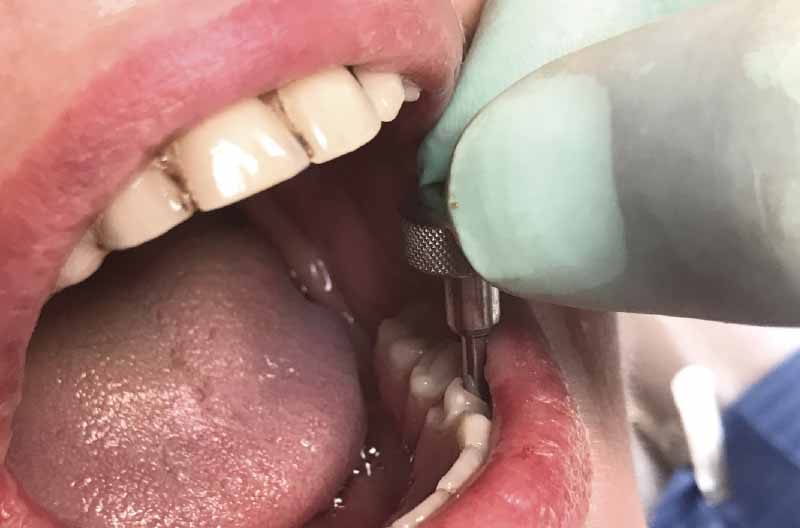

Successivamente preparo i siti implantari in corrispondenza di 32 e 42 seguendo una direzione assiale per alloggiare due impianti Leone 3,3 x 10 mm (Figg. 18-21).

- Fig. 18

- Fig. 19

- Fig. 20

- Fig. 21